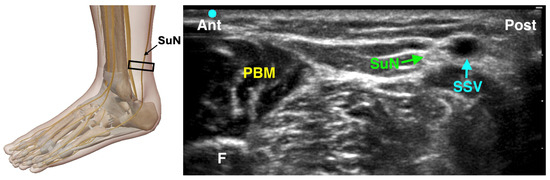

4.3.5. Sural Nerve Block

The sural nerve provides sensory innervation to the lateral aspect of the foot, including the lateral malleolus and fifth toe. It typically runs posterior to the lateral malleolus, adjacent to the small saphenous vein [30,31]. The landmark-based technique involves a semicircular subcutaneous injection of 3–5 mL of local anesthetic, 2–4 cm above and behind the lateral malleolus, from the fibula to the Achilles tendon. Although the nerve is very superficial (about 0.5 cm deep), ultrasound guidance offers greater reliability than landmarks alone. For the ultrasound-guided block, the patient is positioned laterally or with the leg internally rotated. The probe is placed transversely just posterior to the lateral malleolus to identify the nerve, which is usually lateral to the small saphenous vein (Figure 7). Distally, the nerve can be seen ‘rolling’ off the Achilles tendon into a boat-shaped space behind the fibula [32]. Using an in-plane technique, a 22–25 gauge needle is advanced anterior-to-posterior and 1–3 mL of local anesthetic is injected around the nerve. If the nerve is not clearly visible, a perivenous injection near the small saphenous vein may still be effective. Due to its variable distribution—sometimes extending to the third toe or medial heel—the sural nerve block may not be indicated for surgeries involving the first and second toes but can improve comfort for lateral foot or ankle procedures.

Figure 7. Ultrasound-guided Sural Nerve Block. SuN: Sural Nerve; SSV: Small Saphenous Nerve; PBM: Peroneus Brevis Muscle; F: Fibula; The black rectangle indicates the placement of the ultrasound probe on the anatomical area.